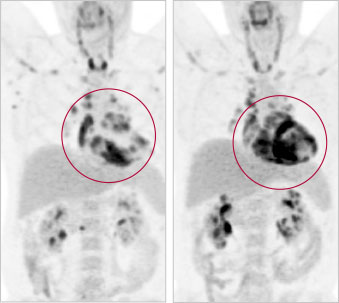

PET scan of cardiac sarcoidosis

There are three main tests for diagnosing cardiac sarcoidosis. The first is a CT scan of the thorax that will reveal enlarged lymph nodes. The second is an MRI scan that will usually show early signs of scarring in the heart tissue. The last test is called an FDG-PET scan, which is a nuclear cardiology test wherein the patient is injected with a radioactive tracer to highlight inflammatory cells in the heart through their uptake of glucose. FDG-PET is available at only a handful of institutions—the Heart Institute being one of them. It provides a more precise image of the heart tissue to better diagnose the condition.

A key component of the cardiac sarcoidosis program at the Heart Institute is the collaboration with imaging, in particular with the PET imaging team lead by Rob Beanlands, MD, Division Head of Cardiology. “High quality PET imaging is so critical to being able to diagnose and manage these patients,” said Dr. Birnie. “We are very fortunate to have world leaders in this area right here in our own National Cardiac PET Centre. It also makes for a very fertile research environment.”